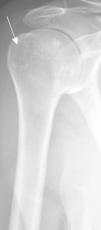

La figura 1 muestra la apariencia típica del pseudotumor deltoideo (flecha). Este término se usa para definir un espectro de variantes en la inserción distal del deltoides, cuya etiología es aún desconocida. Se cree que puede tener la misma etiología que otras variantes como pits sinoviales, irregularidad por avulsiones corticales, por tendinopatía o entesopatía o fenómenos de tracción1. En radiografía simple se muestra como un engrosamiento o irregularidad cortical con densidad y morfología variables2,3. Suele ser asintomático aunque, en muy raras ocasiones, puede provocar dolor1,2. En los casos en los que la apariencia es típica la imagen en radiografía simple es patognomónica (engrosamiento cortical regular, con borde liso y bien definido en el lugar de inserción del deltoides) y no es necesaria la realización de pruebas de imagen adicionales ni seguimiento4.